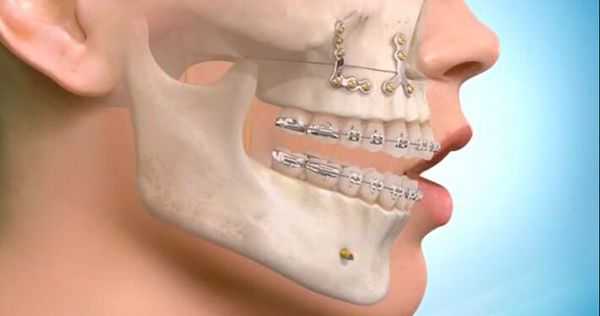

Лечение перелома нижней челюсти заключается в сопоставлении отломков и их фиксации. Иммобилизация обеспечивается проволочными назубными шинами, проволочными или полимерными нитями, остеосинтезом металлическими стержнями, а также с помощью специальных аппаратов. Раны ушивают, при обширных дефектах накладывают проволочные пластиночные швы. Важно обеспечить питание больного высококалорийной пищей, вводимой с помощью поильника или чайной ложки. Для предотвращения травматического остеомиелита вводят антибиотики.

Самым частым методом ортопедического лечения переломов является двучелюстное шинирование — наложение на зубные ряды шин-скоб с репозицией отломков и фиксацией прикуса в привычном для больного положении. Этот метод консервативен и малотравматичен, но в ряде случаев не позволяет получить хорошей фиксации фрагментов верхней челюсти, особенно при высоких и сложных переломах. В среднем при переломах верхней челюсти требуется обездвиживание и ограничение жевательной нагрузки на срок 4-5 недель.

Самым современным и адекватным методом лечения на данный момент является остеосинтез (фиксация титановыми накостными конструкциями) переломов верхней челюсти. Это хирургическое вмешательство, выполняемое из внутриротовых разрезов. При таком варианте лечения можно точно сопоставить и зафиксировать фрагменты для создания условий их сращения [7] .

На челюсть со стороны повреждения накладывается специальное пластиковое устройство или конструкция из проволоки. При травме с обеих сторон кости используется более сложное и жесткое изделие. После установки конструкции в области улыбки формируется череда петель. Крючки на верхней и нижней челюсти соединяются резинками.